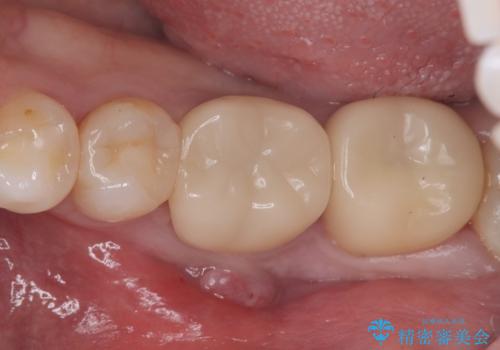

保存が難しい左下6番目の歯を抜歯し、左下8番目の歯(親知らず)を抜歯窩に移植しました。歯牙移植後の動揺防止のため暫間固定を行っています。

骨との定着を確認し、今後矯正治療を行う予定のためレジン冠をセットしています。